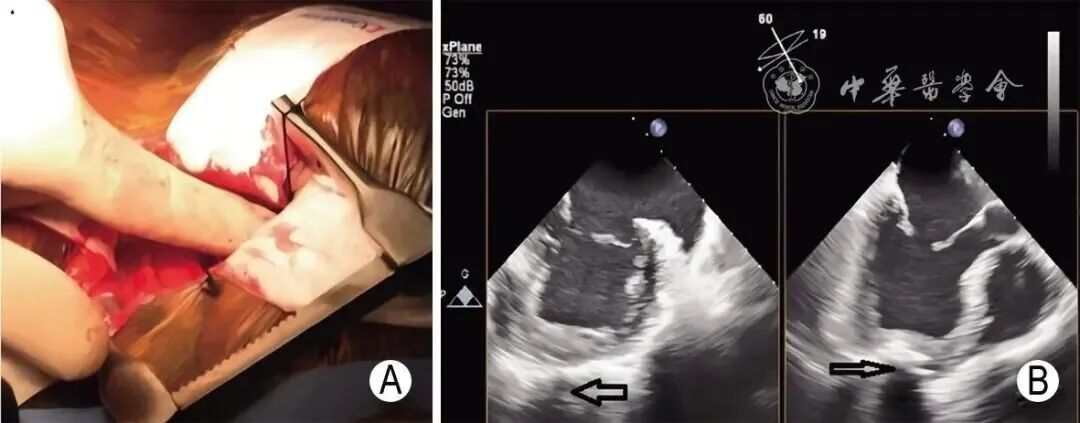

3. 经心尖M-TEER手术规范流程及超声引导切面

经心尖入路M-TEER的超声引导原则与经股静脉入路基本一致,但入路建立阶段(如心尖穿刺定位)的影像导航存在差异;而夹合器捕获、释放等核心操作环节的关键工作切面和超声评估技术与经股静脉M-TEER类似,手术流程和超声引导切面总结见表8,图15~19。

图15 经心尖入路选择最佳穿刺点 A:指尖按压法选择经心尖入路最佳穿刺点;B:经TEE X-plane切面显示指尖压迫点